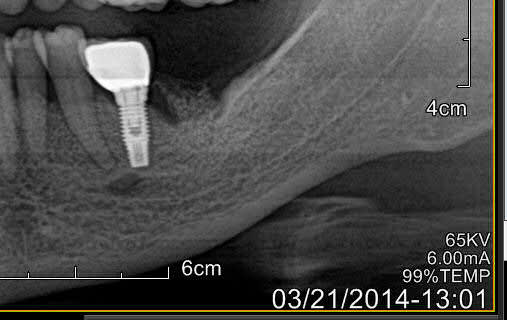

Concernant la force pour ressortir un implant osteointégré, meme ne tenant que sur 4 mm, elle est INCROYABLEMENT FORTE.

J'ai eu le cas sur une patiente avec implants sans probleme depuis 2006, debut de craterisation en 2014.

J'ai utilise le tourne a gauche d'anthogyr, et malgre le detourage a la fraise sur la profondeur la plus grande possible, j'ai bien cru que soit l'instrument soit la mandibule allaient rompre.

En fait ca ressort quand l'os autour de l'implant se rompt dans son epaisseur. L'os est reste collé sur l'implant retire.